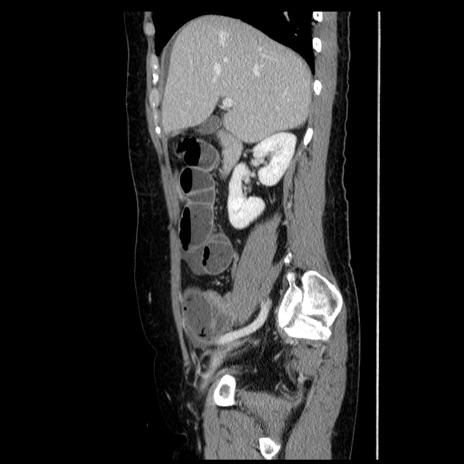

冠状断像

【症例】50歳代女性

【主訴】下腹部痛

【既往歴】卵巣癌術後(8年前に当院で卵巣摘出)

【身体所見】 意識清明、腹部:平坦、腸蠕動音→、やや硬、下腹部自発痛・圧痛あり、反跳痛あり、筋性防御なし。

【データ】WBC 16000、CRP 0.01